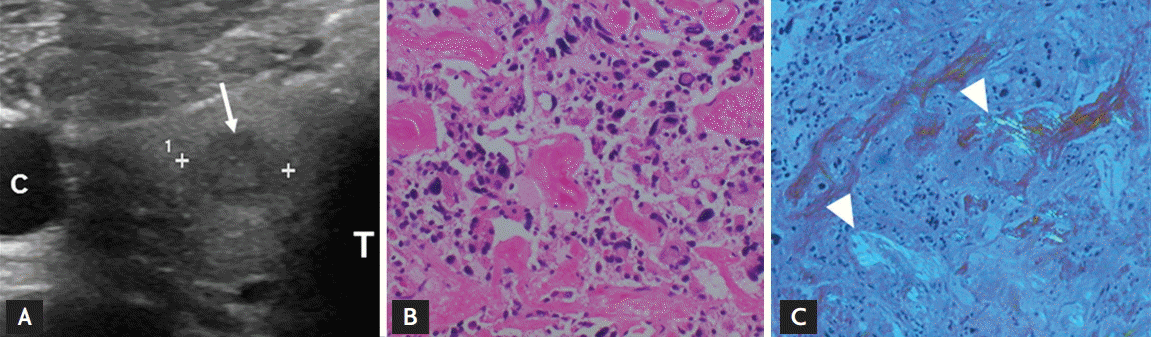

Thyroid ultrasonography during work-up of KD revealed a 7-mm hypoechoic nodule in the right lobe (Fig. 2A). Fine needle aspiration (FNA) cytology initially found severe atypical cells of uncertain significance, and, after recovery from KD, repeat FNA detected poorly differentiated carcinoma, which prompted surgery. The calcitonin level measured by chemiluminescence assay was 16.3 pg/mL (normal range in male, < 11.8), which was confirmed on repeat testing. The serum carcinoembryonic antigen of 2.6 ng/mL was within normal limits. Subsequently, bilateral total thyroidectomy and central lymph node dissection were performed. Since RET germline mutation analysis was negative and the patient had no family history of multiple endocrine neoplasm type 2 syndrome, we did not perform presurgical biochemical testing for co-existing tumors (particularly pheochromocytoma and hyperparathyroidism). Histopathology (Fig. 2B and 2C) confirmed a 5-mm medullary thyroid cancer (MTC) via positive immunohistochemical staining of chromogranin A, thyroid transcription factor-1, and synaptophysin and by staining of deposited stromal amyloid with Congo red. Two months after surgery, the patient’s calcitonin level was undetectable (< 1.0 pg/mL).

Figure 2.

(A) Ultrasonography of the right thyroid lobe revealed a 7-mm hypoechoic nodule (arrow). (B) Surgical section of medullary thyroid cancer (MTC) with polygonal or spindle cells in nests or follicle formation. Tumor cells displayed granular cytoplasm with oval nuclei. The stroma contained amyloid deposits (H&E, ×200). (C) Congo red staining of MTC showed apple green birefringence (arrowheads, ×100). C, carotid artery; T, trachea.